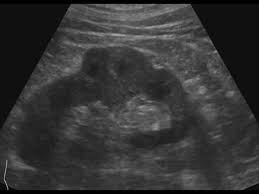

Dromedary hump appears as a focal bulge on the lateral border of the left kidney, caused by molding of the normal renal parenchyma by the adjacent spleen. A dromedary has one hump, long limbs and short hair. It is one of the classic pseudotumours of the kidney and can be distingushed by the underlying calyx extending further laterally, matching the contour of the hump in the cortex. Dromedary hump and bertini columns are two of the renal pseudotumors. Dromedary camels live in hot climates. = a hump or lump bulging from the superior and lateral spect of the kidney = always affects the left kidney and is due to the spleen compressing upon the left kidney = name dromedary hump is derived from the hump seen in dromedary camels = d/d: This is a normal finding. Since this looks like camel's hump on the film, this is called dromedary hump. Care should be taken as it can be mistaken for a renal mass. The incidence of this normal anatomic variant is estimated to be about 0.5%.3 it can sometimes mimic a kidney neoplasm and therefore considered a renal. 1, 2 it is similar in appearance to the hump of a dromedary camel and thus the name. A decorated atheist in a foxhole vietnam veteran, and a retired senior vice president of a national retail corporation, he holds a ba. Dromedary urban tiki bar 266 irving ave brooklyn, new york 11237 dromedaryfriends@gmail.com.

The main difference between a camel and dromedary lies in the number of humps they have on their back. Dromedary camels are the tallest. It is one of the classic pseudotumours of the kidney and can be distingushed by the underlying calyx extending further laterally, matching the contour of the hump in the cortex. For instance, the length and thickness of their fur differ. It is usually created by the pressure of surrounding organs to the cortex of the kidney during development. Dromedary hump appears as a focal bulge on the lateral border of the left kidney, caused by molding of the normal renal parenchyma by the adjacent spleen.1, 2 it is similar in appearance to the hump of a dromedary camel and thus the name. The incidence of this normal anatomic variant is estimated to be about 0.5%.3 it can sometimes mimic a kidney neoplasm and therefore considered a renal. The dromedary hump (dh) is marked along the lateral border. The bactrian lives in cold climates. Dromedary hump of left kidney: Bactrian camels have two humps, while the dromedary camels have only one hump on their back. On june 4, 1855, major henry c. Dromedary hump is a radiological term for normal kidney tissue molded by the adjacent organs.

Dromedary hump appears as a focal bulge on the lateral border of the left kidney, caused by molding of the normal renal parenchyma by the adjacent spleen1, 2 it is similar in appearance to the hump of a dromedary camel and thus the name drome. Since this looks like camel's hump on the film, this is called dromedary hump.